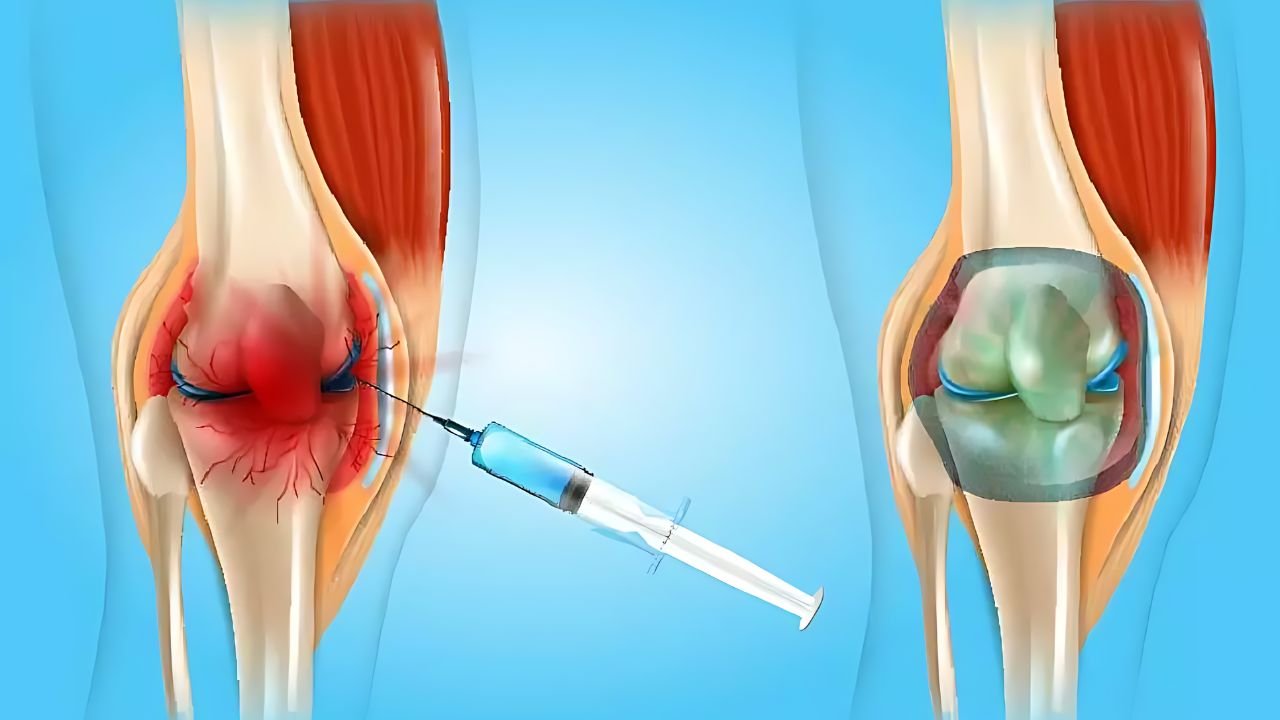

Uma dessas opções de ponta é a viscossuplementação, um procedimento que consiste na infiltração intra-articular de ácido hialurônico. Esta substância é produzida naturalmente pelo nosso corpo, mas sua concentração diminui drasticamente em articulações afetadas pela artrose, resultando em atrito e dor constante.

O objetivo central deste tratamento é devolver a lubrificação mecânica e o amortecimento ao joelho. Ao injetar o ácido hialurônico de alta densidade diretamente na articulação, criamos uma camada protetora que reduz significativamente o impacto entre os ossos, aliviando a inflamação e melhorando o deslizamento articular.

A aplicação é um procedimento rápido, seguro e realizado no próprio consultório. Para garantir precisão milimétrica e maximizar os resultados, a infiltração é feita de forma guiada por ultrassom. Isso assegura que a medicação seja entregue no local exato da lesão, preservando totalmente as estruturas saudáveis ao redor.